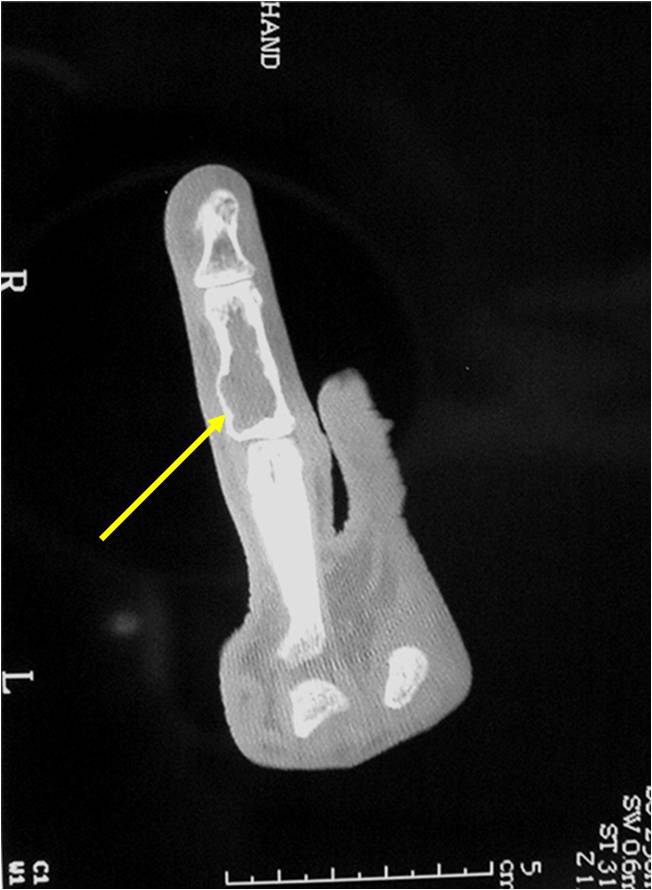

Geographic lesion Stippled calcifications in lesion Phalanx is expanded Significant endosteal scalloping No cortical destruction No soft tissue extension Cortex Scalloped and Expanded